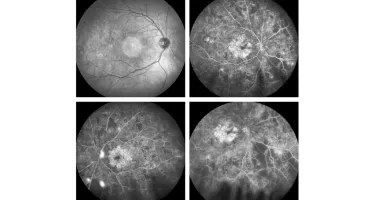

• Schnelles Fortschreiten der proliferativen diabetischen Retinopathie - Matthew D. Bovenzi, OD, FAAO, Jerome Sherman, OD, FAAO, Sherry J. Bass, OD, FAAO